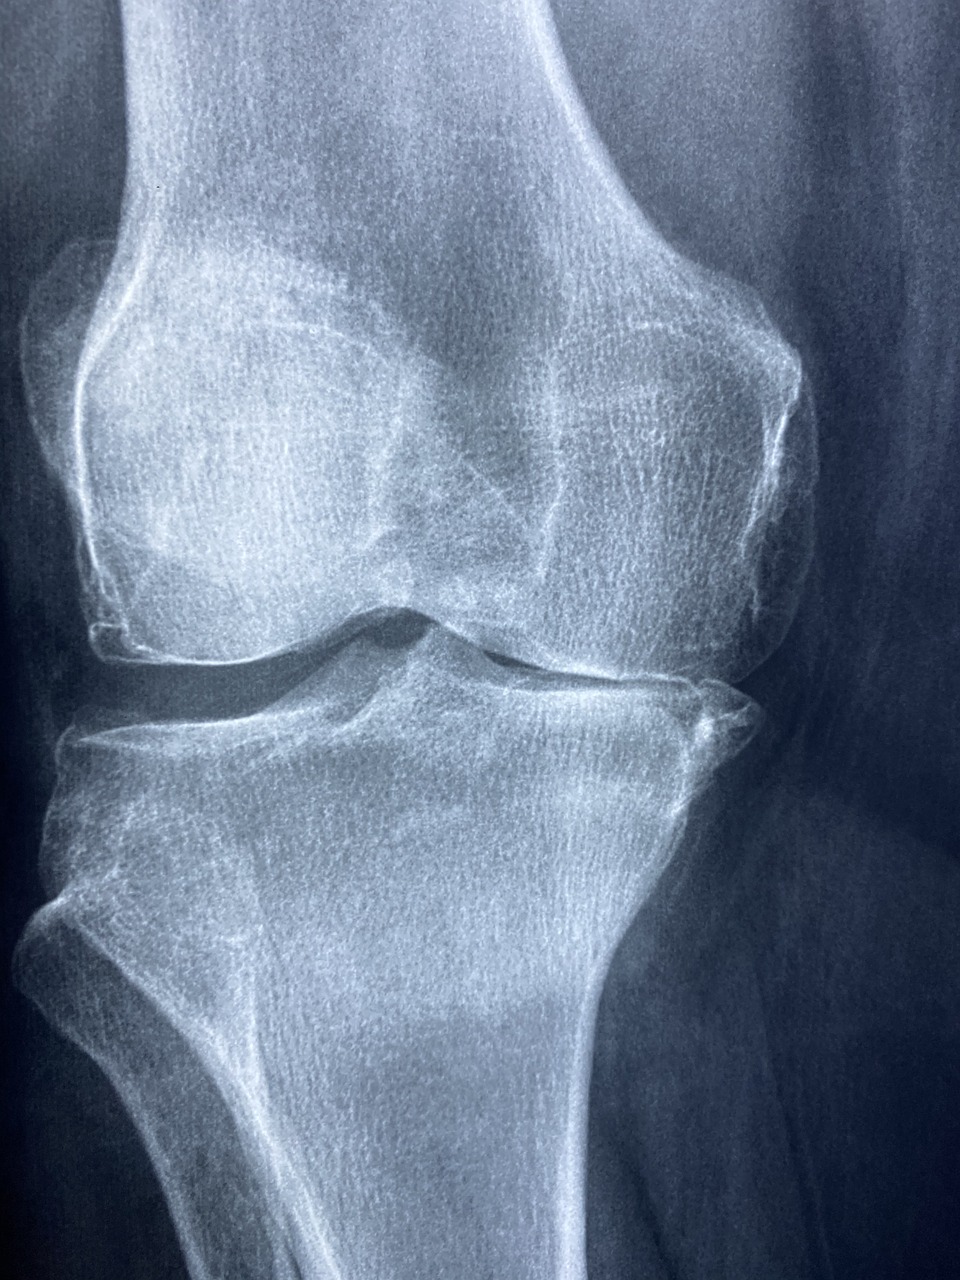

- 슬관절 치환술 후 무릎의 굴곡 제한을 해결하기 위한 수기 가동술 + 유산소 운동 병합